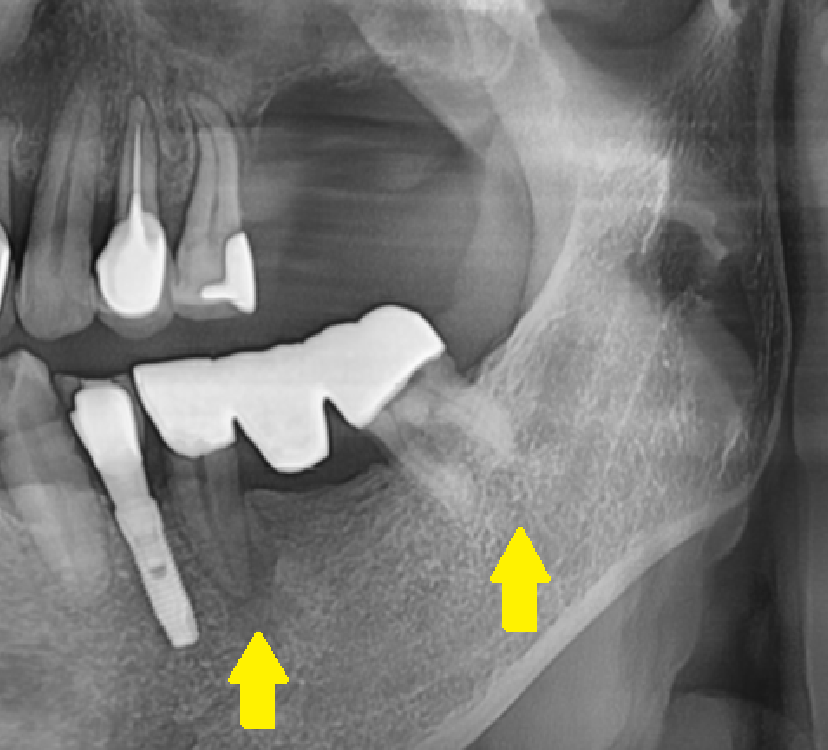

250630 치아가 빠지고 방치하여 정출된 치아

250702 치아 높이 차이를 확인해보세요